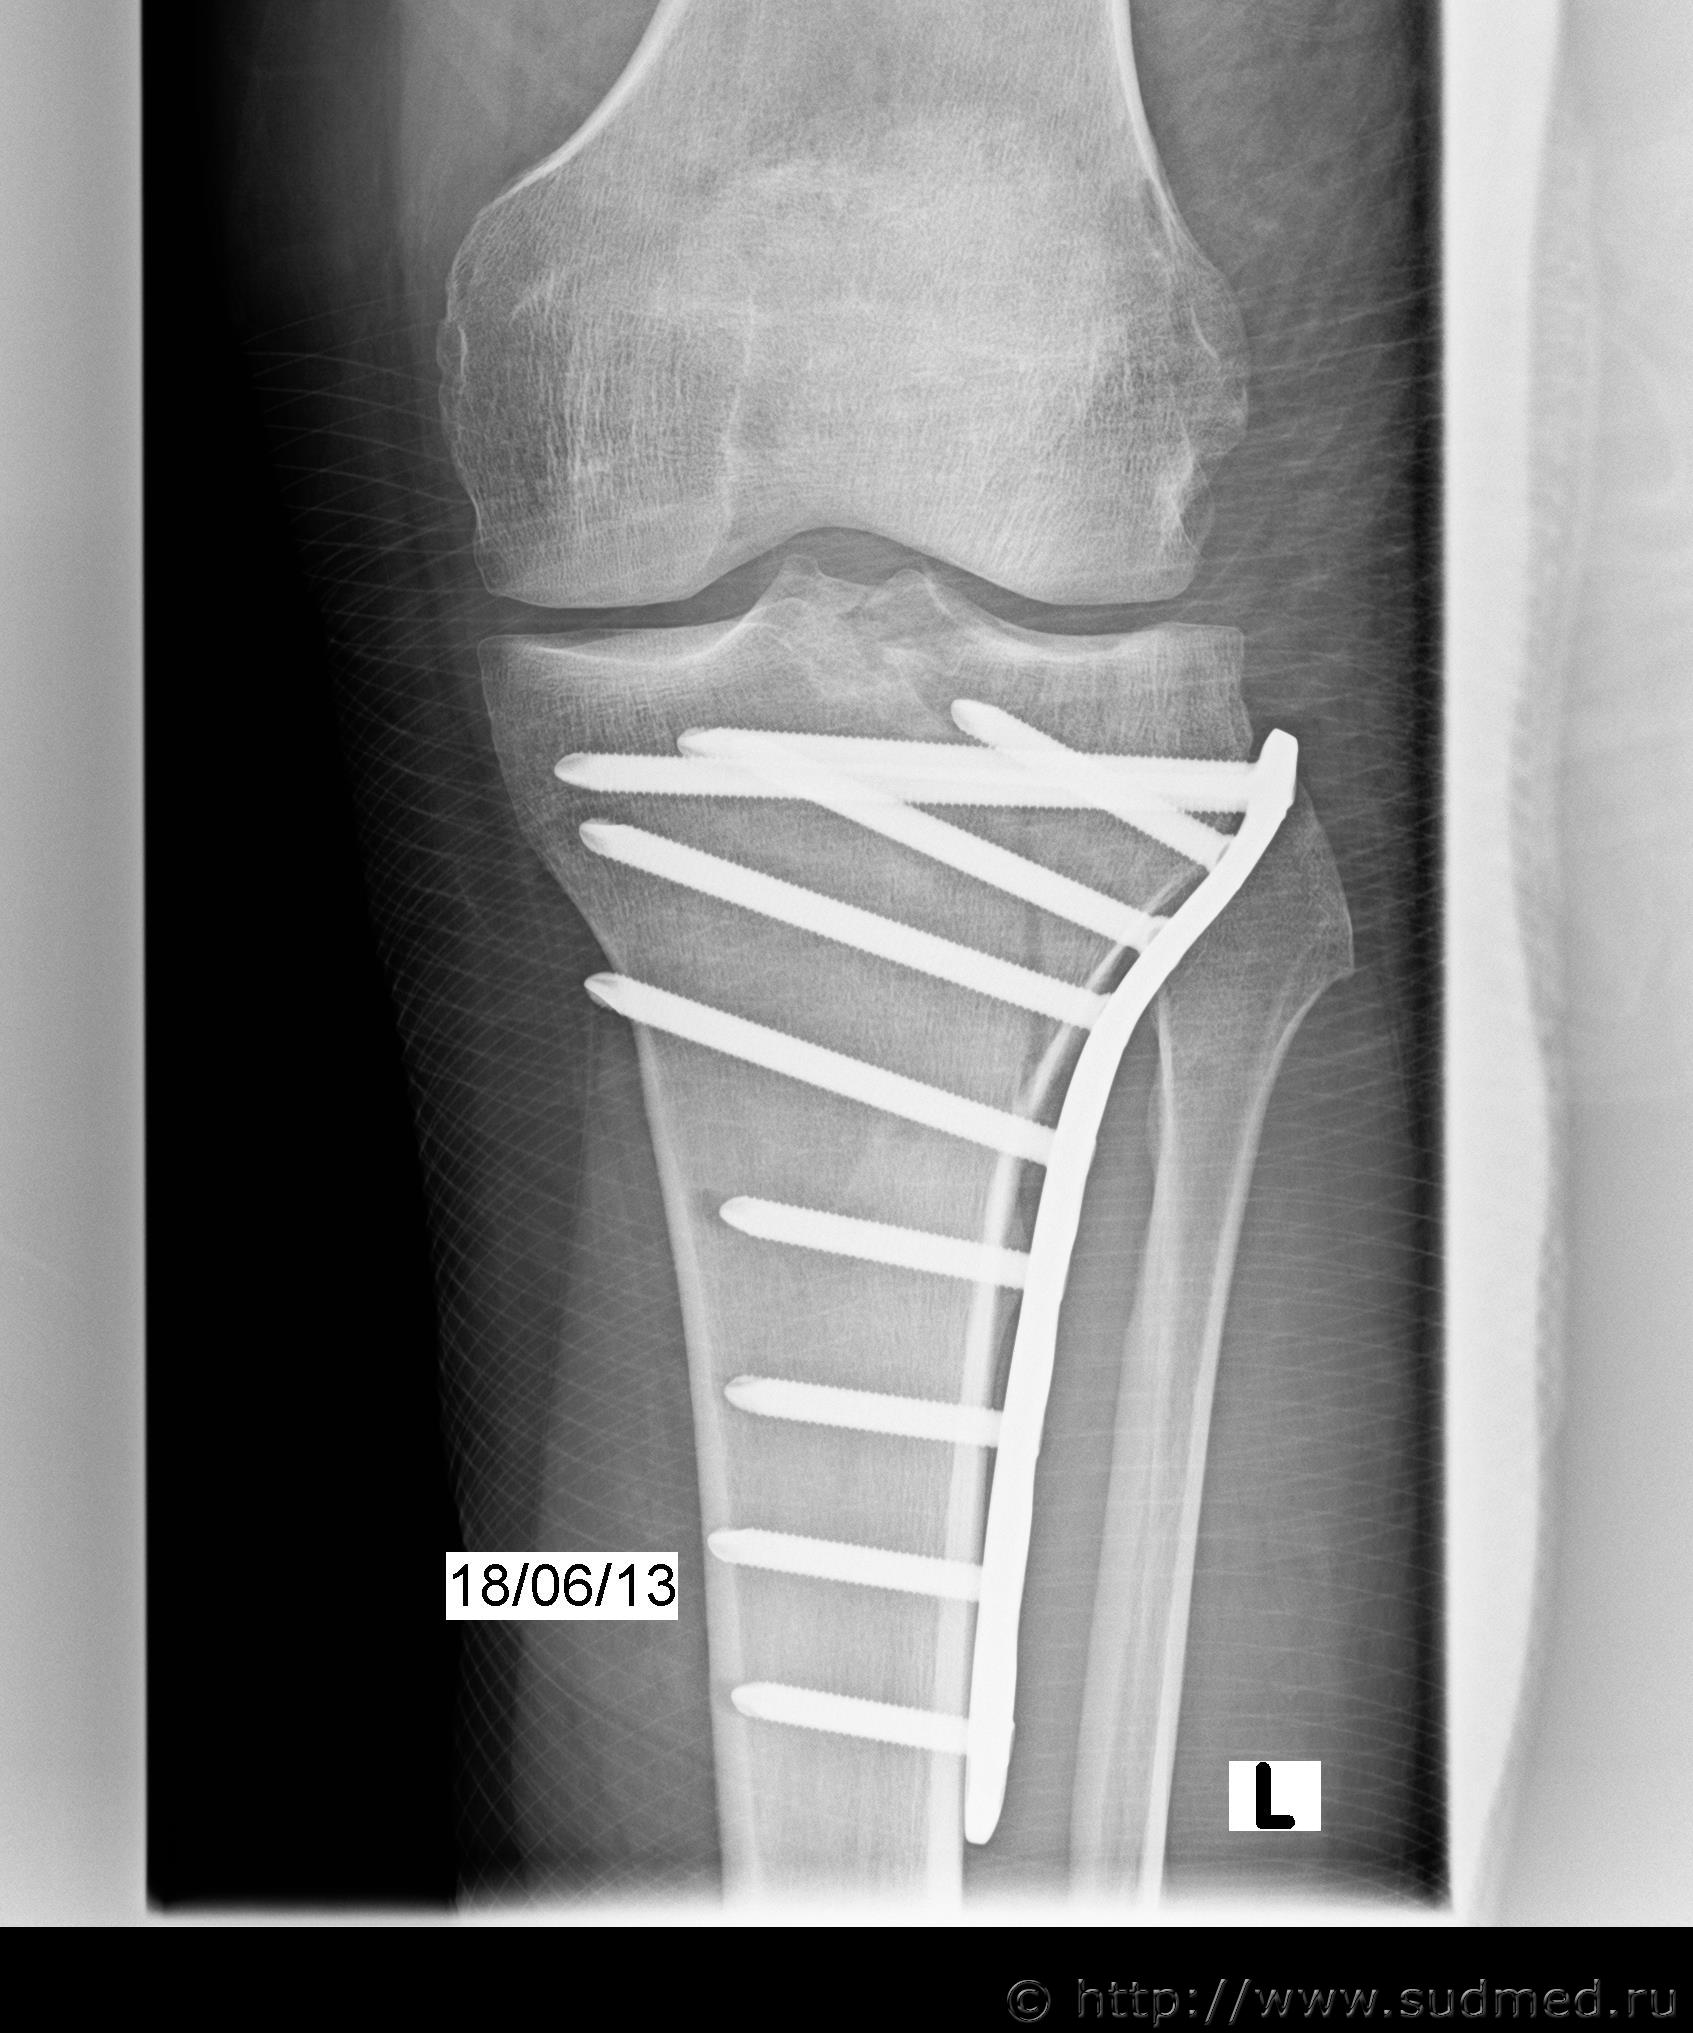

Добрый день! 9 июня мой муж на мотоцикле попал в аварию. Виновным признали второго водителя. У мужа перелом мыщелка со смещением. Делали остеосинтез, костную пластику, лежал в больнице месяц, после этого еще 3 месяца на костылях. До сих пор хромает, колено полностью не разгибается и визуально отличается от здорового. После операции поставили еще и артроз коленного сустава. В больнице врач предупреждал, что возможно будет необходимость в замене коленного сустава. Рентген после операции прилагаю.